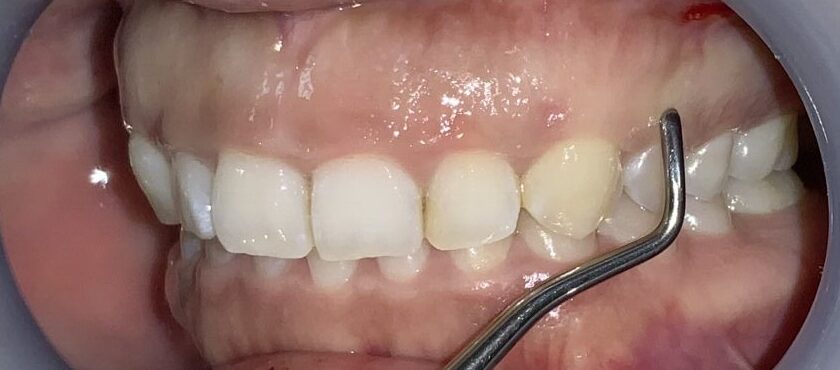

隣の歯も同じように検査します。

隣の歯は前歯ほどではないですが、しっかりと歯ぐきが、かぶっています。

この歯は犬歯です。犬歯もたくさんの歯ぐきに覆われているようですが、治療をする場合には注意が必要です。

犬歯はあまり大きくすると、八重歯のように見えてしまい、せっかくの治療が台無しになる場合があります。また、被っている歯ぐきがたくさんあっても、歯ぐきが薄い場合があり、このような歯ぐきの場合は、治療後に歯ぐきが退縮してしまい、歯槽膿漏の歯ぐきのように見えてしまう場合があります。

難関の犬歯を超えたところで、第一小臼歯の4番面の歯を検査します。

奥歯なのに、歯ぐきがたくさん被っているようです。3番目の犬歯と違い、奥歯の形になってきている4番目の歯は、犬歯とは違う注意が必要です。

この歯は奥歯の形なので、歯ぐきを取りすぎると、知覚過敏になる場合があります。また、前歯と奥歯の間の歯ですから、前歯に比べて治りが遅い傾向にあります。歯ぐきの切除も慎重に行わなければなりません。